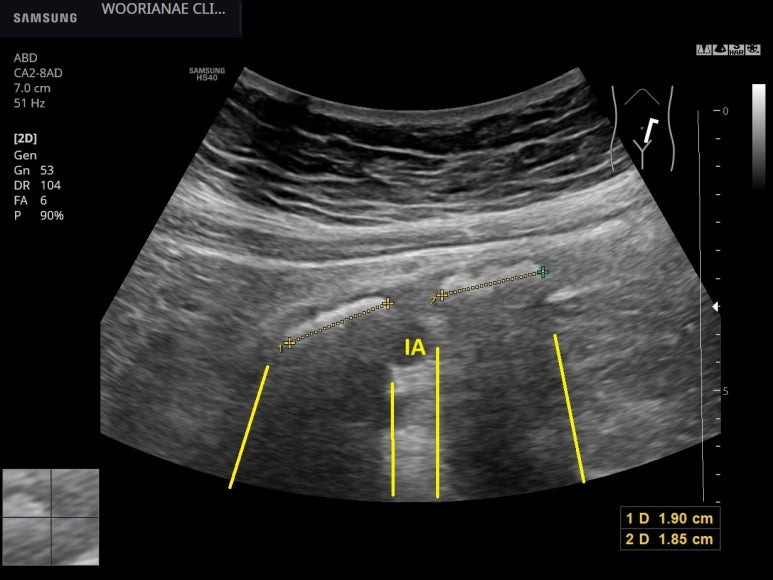

그런데... 오히려 복부 앞쪽에서 훨씬 뚜렷히 관찰된다.

IA; 장골동맥, 왼쪽

twinkle 효과

WOW... 장골동맥과 교차하는 곳이 상대적 협착부위여서 위쪽에 결석들이 있는데, 바로 아래에도 하나가 더 있고 크기가 2 cm에 육박한다. 수년간 본 결석중에 매우 큰 경우

역시나 twinkle 효과